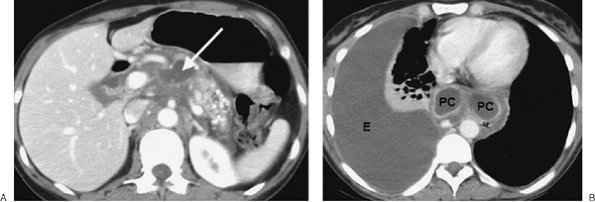

FIGURE 6-38. Mediastinal pancreatic pseudocysts. A: CT scan of a 39-year-old man with acute and chronic pancreatitis shows cystic areas within the pancreas (arrow) and pancreatic calcifications. B: CT scan at a more superior level shows rim-enhancing pancreatic pseudocysts (PC) within the posterior mediastinum and a large right pleural effusion (E).